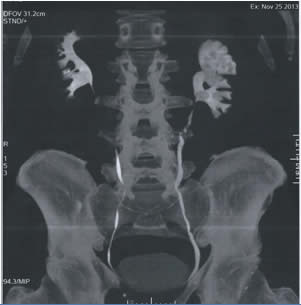

Αυτή η δυνατότητα είναι πολύ σημαντική σε περιπτώσεις με λίθους σε κάθε σημείο του νεφρού όπως στην φωτογραφία.

Η μέθοδος είναι ότι καλύτερο έχει να προσφέρει η σύγχρονη ουρολογία στη πάθηση της νεφρολιθίασης. Εφαρμόζεται από εξαιρετικά εξειδικευμένους χειρουργούς και απαιτεί κατάλληλο τεχνολογικό εξοπλισμό και τεχνογνωσία.

Προσφάτως στην χώρα μας εφαρμόζεται από εμένα και την ομάδα μου με απόλυτη επιτυχία σε δύσκολες περιπτώσεις.